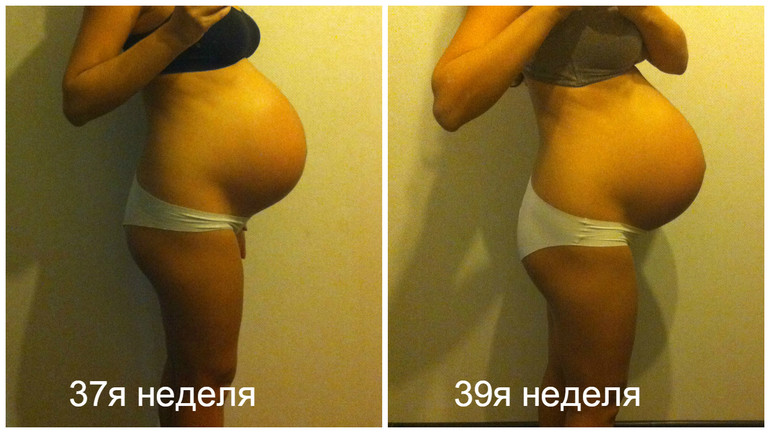

Тошнота на 37 неделе беременности: причины и рекомендации